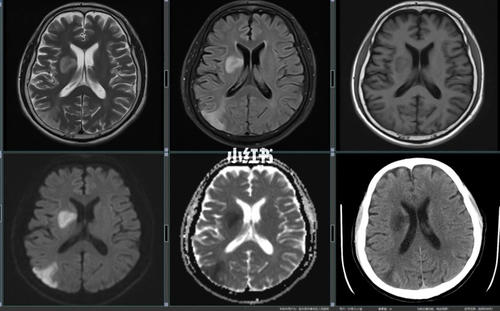

在核磁片子上怎应区分脑梗塞的新旧病灶

。你好,这个要看它们的密度区分新灶比较清晰旧灶比较暗

小脑新发的梗塞,一般会有走路不稳等共济失调的症状,如果在发病早期(24小时内),去医院做CT,会发现报告和症状不匹配。临床症状强烈支持小脑梗塞,可为什么CT... 上...